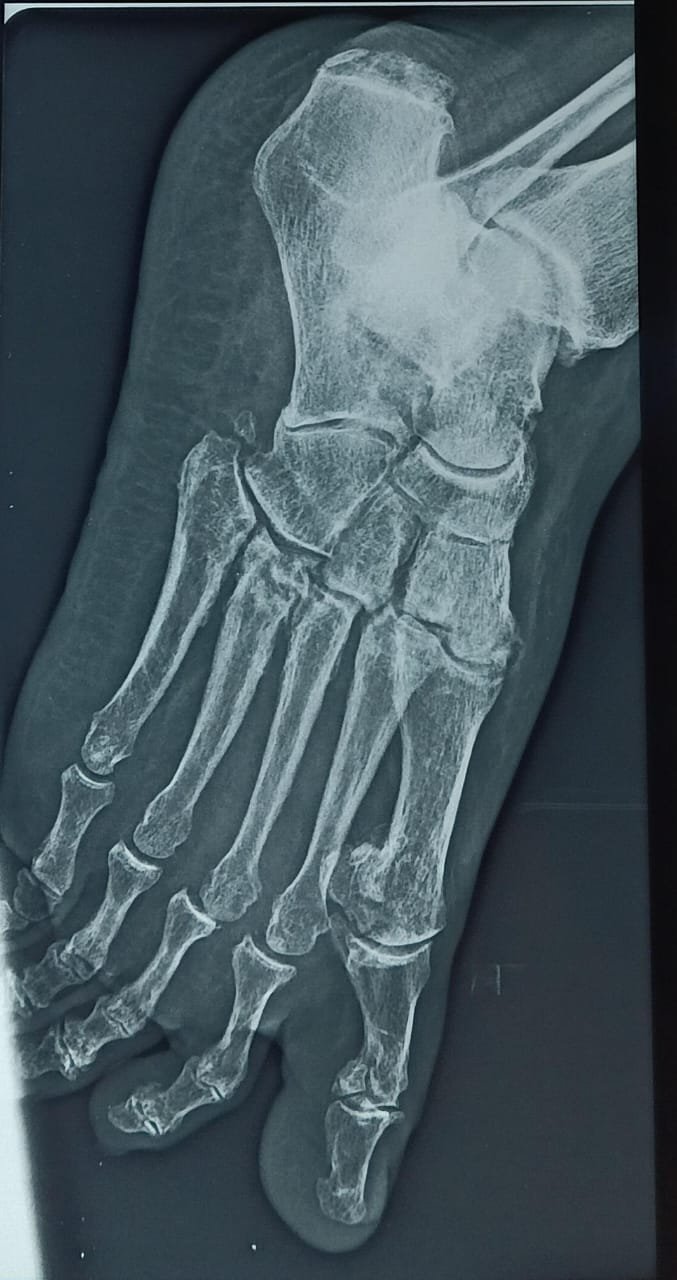

Lisfranc Injury

Atlas ID: 2 • Orthonotes Atlas

Lisfranc Injuries

Lisfranc Injury - Case Based Learning

Lisfranc Injury. Orthonotes Atlas. The Bone Stories. Available at: https://orthonotes.in/atlas/lisfranc-injury-69b949996a781 Accessed: 2026